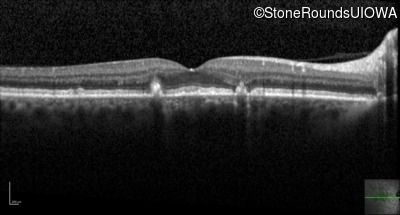

Optical Coherence Tomography - Right - 20/20 -1 sc

Exemplar / OCT Stack